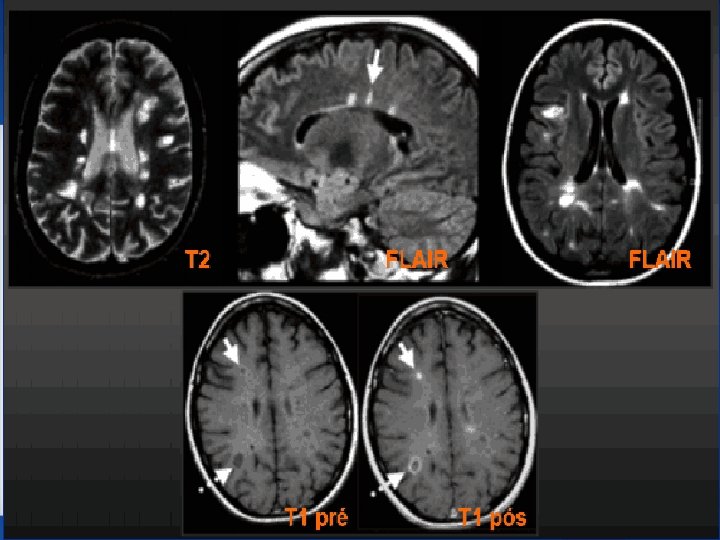

DIAGNÓSTICO • História – Episódios prévios (Sd clínica isolada) – História familiar • Exame físico – Evidência objetiva (Sd neurônio motor superior) • Testes adicionais – MRI – CT – Banda oligoclonal – Potencial evocado visual

T 1 PRÉ/PÓS CONTRASTE